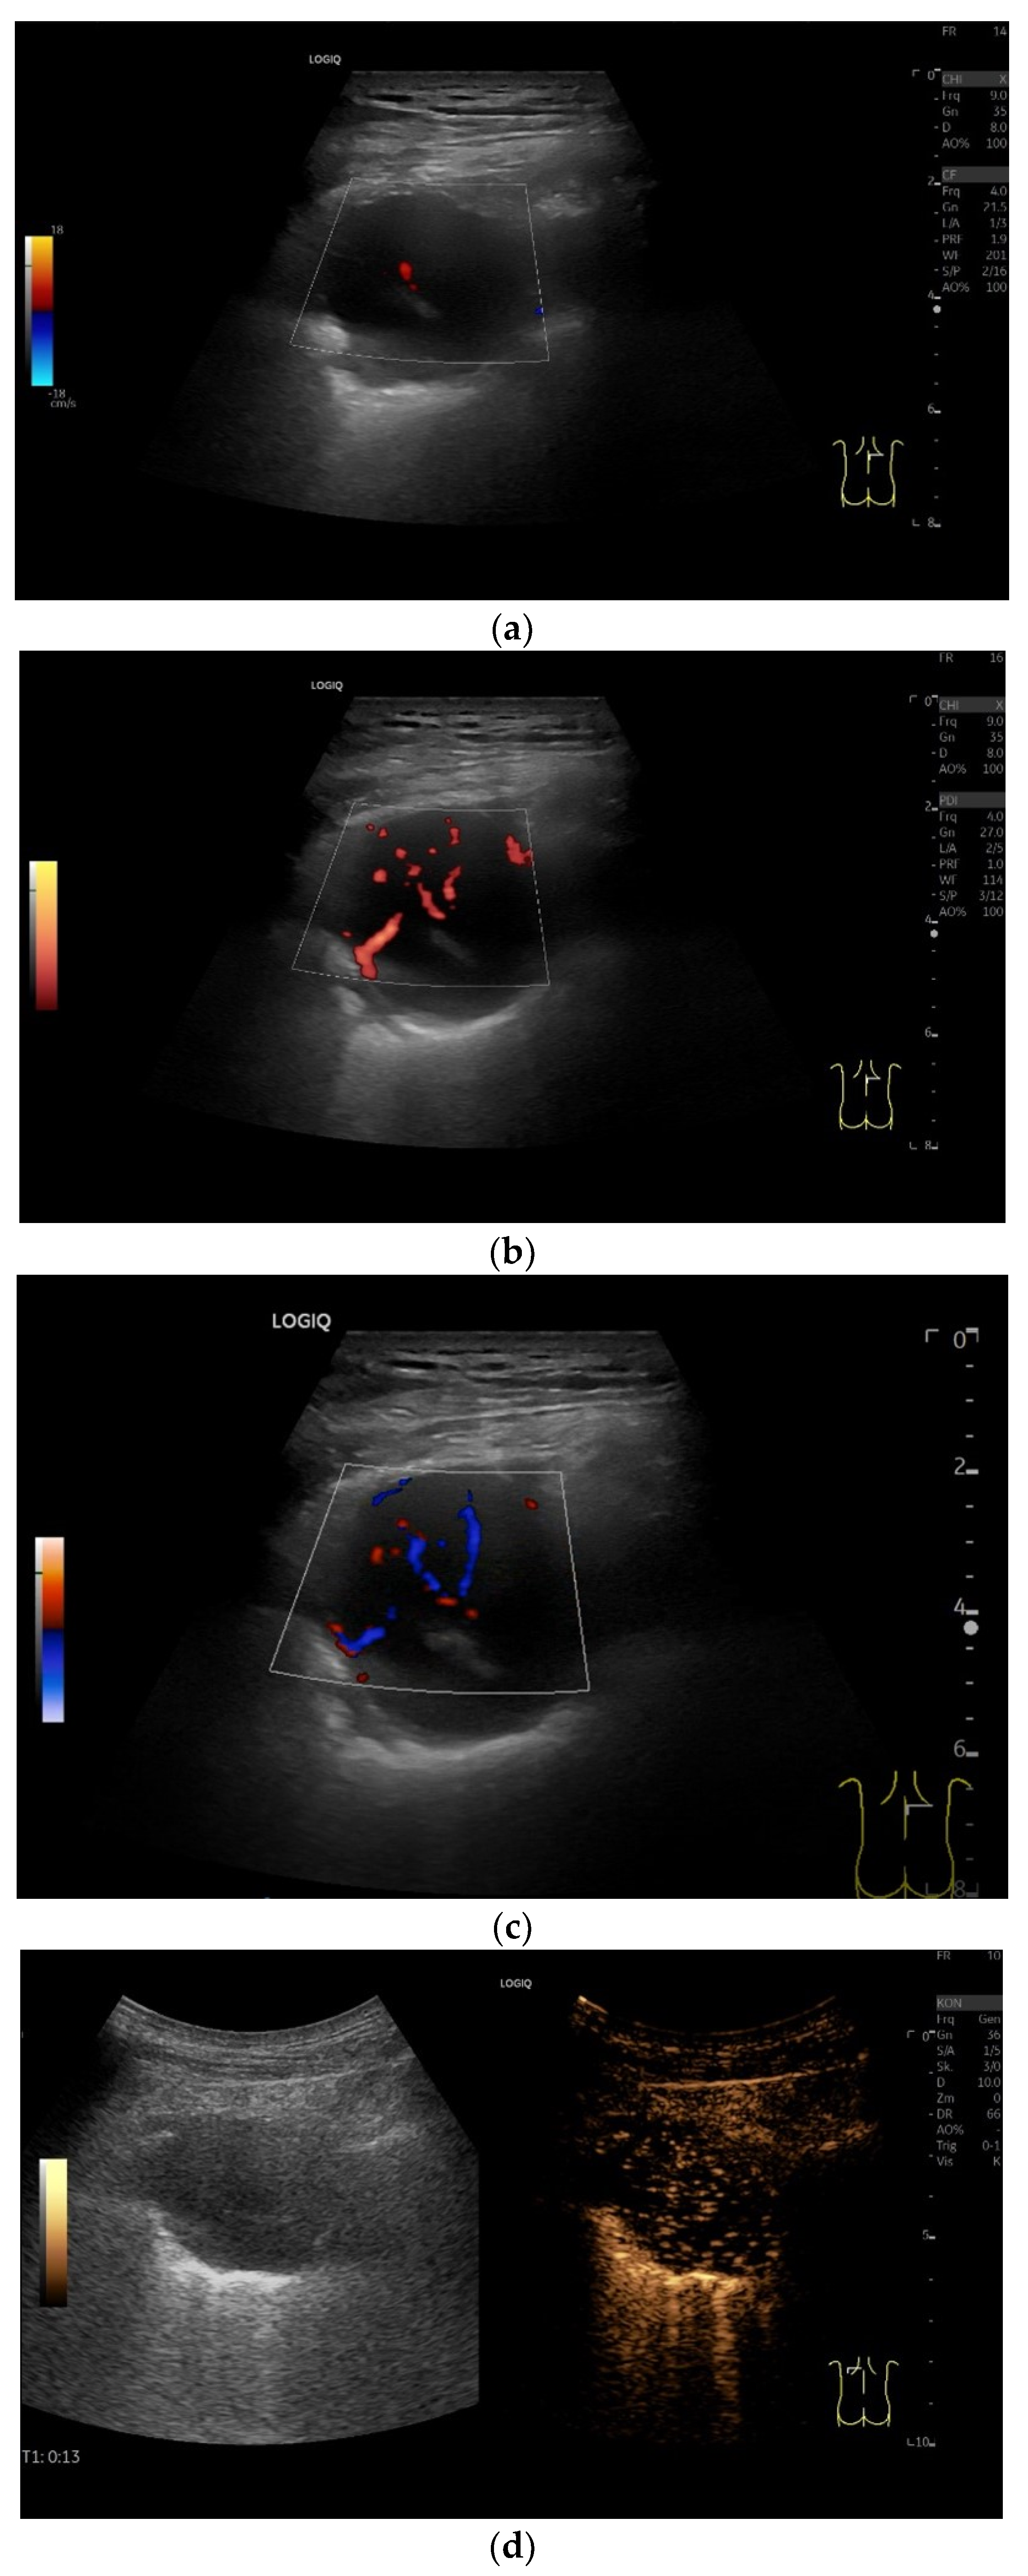

| Solitary extramedullary plasmacytoma | Round, hypoechoic tumor. Macrovessels on CDI. Homogeneous hyper-enhancement on CEUS. |